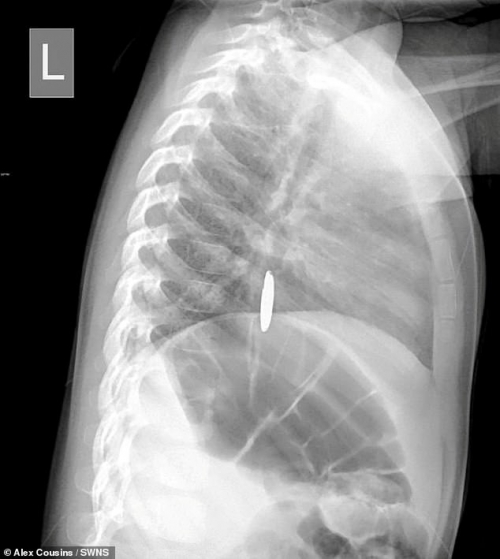

أشعة بطاريه ألعاب

أشعة بطاريه ألعاب

ووفقا لتقرير لصحيفة "ديلى ميل البريطانية"أكد الأطباء أن الأم كانت تظن أن طفلتها ابتلعت عمله نقود ولكن تبين أن الطفلة ابتلعت بطارية ليثيوم وظلت مثبتة في أعلى المريء فى منطقة الصدر.

وقال الأطباء إن البطارية كانت تحترق بسرعة في حلق الطفلة وهو ما قضى على حياتها فى غضون وقت صغير نتيجة للحروق التى أحدثتها فى حلقها.